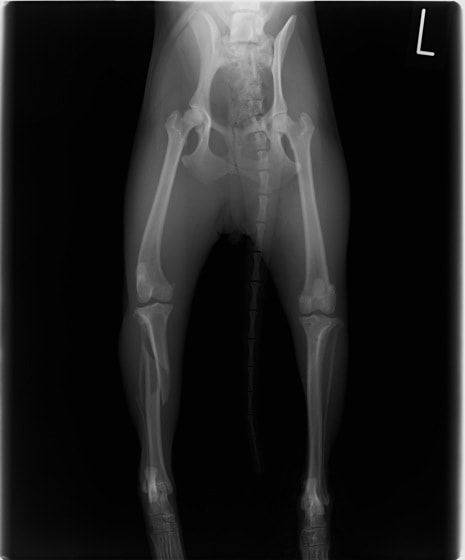

骨盤骨折 : 症例1 | 症例2 | 症例3 | 症例4

脛骨骨折 : 症例1 | 症例2 | 症例3 | 症例4 | 症例5

大腿骨遠位端骨折 : 症例1 | 症例2

成長版骨折 : 症例1 | 症例2